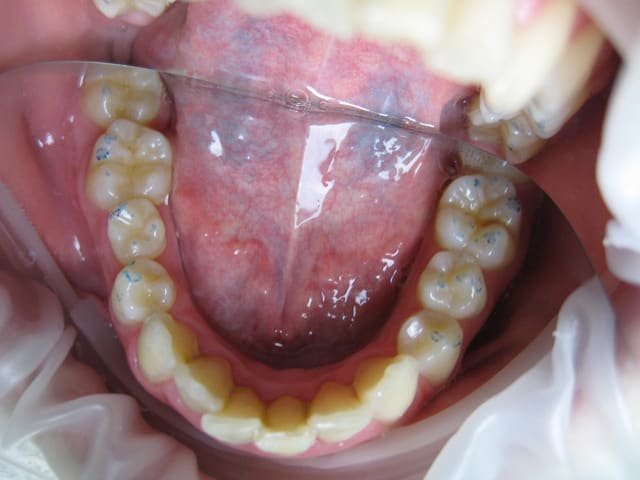

Voici les photos, radios et moulages du cas

pour le stephenson, mon avis qui n'engage que moi, tu peux oublier.

Le maxillaire n'est pas si avancé que cela, par rapport a mac namara ( mais c'est normale, si c'est la base du crane qui est augmenté ) : donc : chirurgie pour raccourcir la base du crane ?

La mandibule semble un peu en retrait, au niveau profil : peut-etre encore possible de mettre un propulseur type PUL, mais à 14 ans pour une fille, c'est limite.

Sinon, extraction 14 24, c'est quand même moins lourd qu'un Lefort.